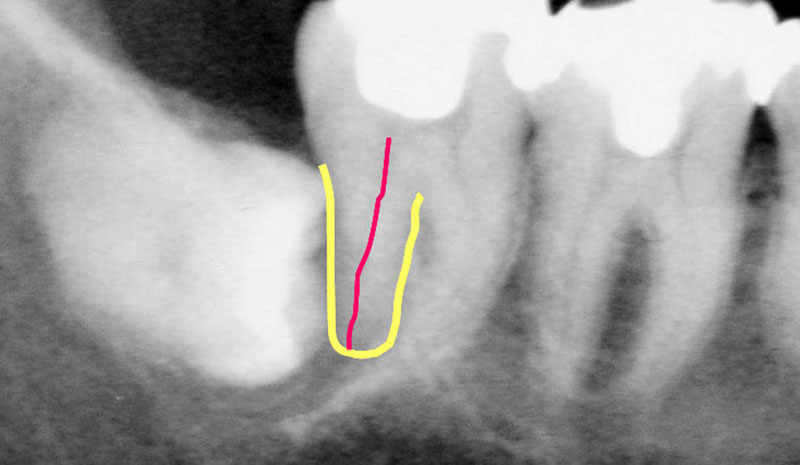

さあ、次のレントゲン写真です。赤いのは歯の神経です。

わかりやすく手前の7番目の歯の後ろ側の根と神経血管部分にラインを引いています(本来は右の歯のように神経血管が通っているトンネルの状態ですので、黒い線となって写ります)。

「親知らず」8がお隣の6番目の歯、7番目の歯に対して横にむいてきてるわけですね。

今後どうなると思いますか?神経が圧迫されて痛いのです。

横に倒れていますから、自然に待っていても絶対生えてきませんね。

ほっといても上向きに出てこないですから、生えてきたら抜きましょう、歯茎に隠れてるから抜くのたいへんですから、腫れますからっていって置いておくと、こんな風になってしまうのです。

どうなってしまったか?

わかりますか?

親知らずによって、手前の歯の神経がちょんとブチ切られていますよね。

昔のゲームに「パックマン」ってありましたよね。

そんなイメージでしょうか。食べられてしまっています。

ものすごく痛がりますよね、この患者さんは。

とても痛いと思います。

歯の神経血管は顎の後ろから顎骨の深い部分中を通って歯の根から入っていきます。

ここをちょんと切られるわけですから、とんでもなく痛いのです。

「何とか歯を残してください、親知らずを抜きますから」と患者さんはおっしゃいました。

しかし、すでに7の神経が切れていますから、指が切れて落ちてるわけですから、死んだ人をよみがえらせてって言われても残念ながら手遅れなのです。

無理なのです。

なので、「親知らず」は他の歯に影響が出る前に抜いたほうが良いと私は思っています。